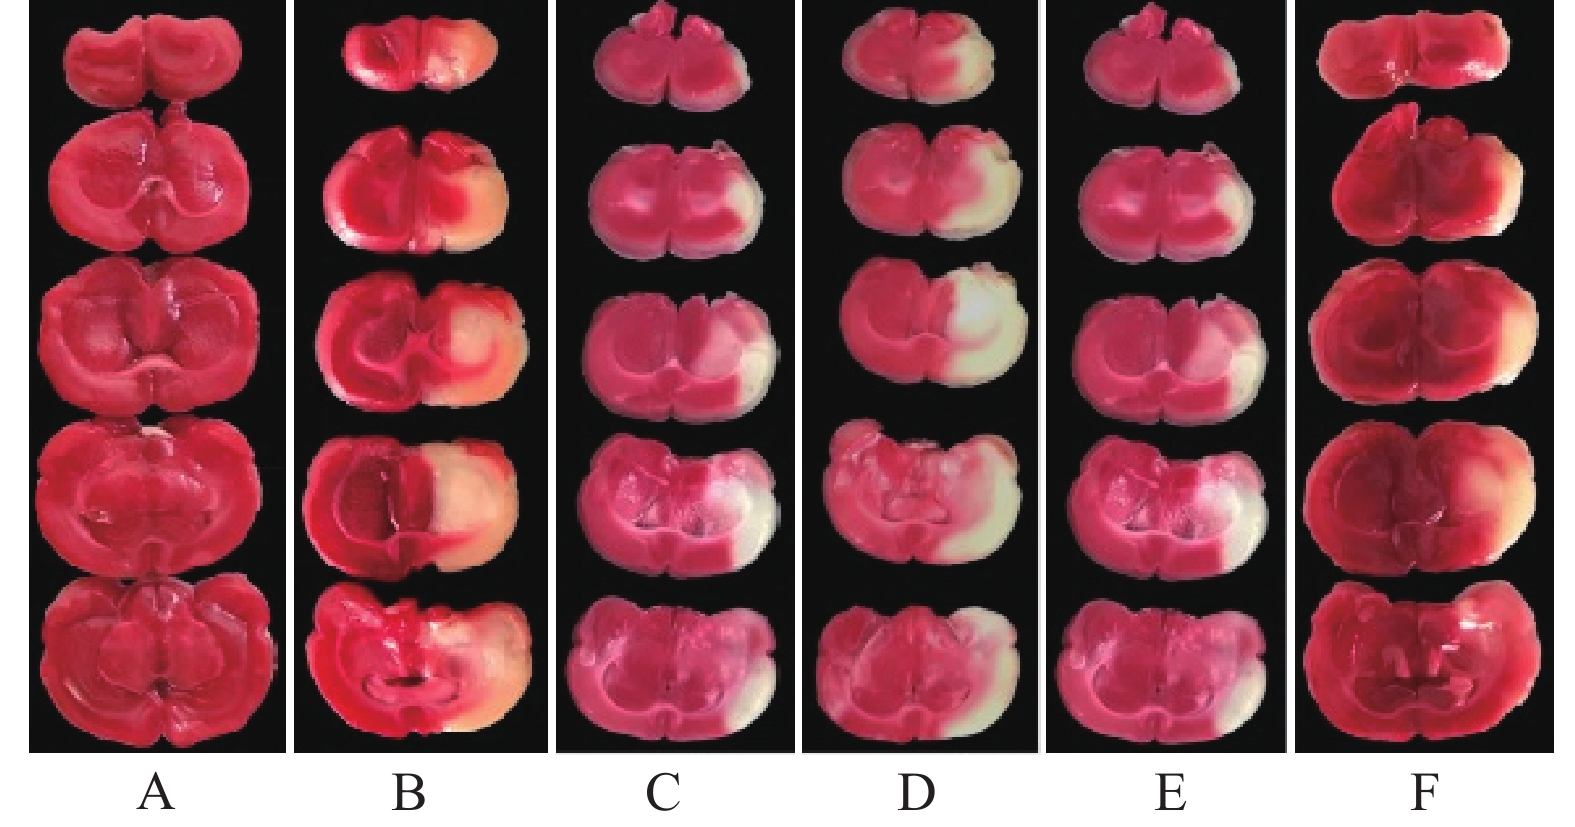

Objective To investigate the effect of triptolide on cerebral ischemia- reperfusion injury (CIRI) and explore its molecular mechanism. Methods One hundred and forty-four Wistar rats were randomly divided into sham operation group, model group, low, medium, high dose of triptolide group and butylphthalide group, with 24 rats in each group. The CIRI rat model was established by blocking the middle cerebral artery for 2 hours. 3 days before modeling, the rats in each group were ip administration once a day. 24 hours after reperfusion, the neurological deficit score was detected, the rate of cerebral infarction was measured by TTC staining, the blood brain barrier (BBB) permeability was detected by EB penetration test. The pathological changes neurons in the ischemic penumbra cortex were observed by HE and TUNEL staining. The content of inflammatory factors in ischemic cerebral cortex were detected by Elisa method. The expression of TLR4/NF-κB pathway related proteins were detected by Western blot. Results Compared with the model group, the neurological deficit score, cerebral infarction rate and EB content in the triptolide middle, high dose groups and the butylphthalide group were significantly decreased (P<0.05). The pathological changes of cortical neurons in the ischemic penumbra were significantly improved, and the apoptosis rate of neurons was significantly decreased (P<0.05). The content of TNF-α, IL-1β and the expression of TLR4, p-NF-κB, cleaved caspase-3, Bax were significantly decreased, the expression of Bcl-2 was significantly increased, the ratio of p-NF-κB/NF-κB and Bax/Bcl-2 were significantly decreased (P<0.05). The regulatory effect of the high dose triptolide group on various detection indexes were better than that of the butylphthalide group (P<0.05). Conclusion Triptolide could protect the permeability of BBB, improve the neurological deficit and neuropathy in CIRI rats, and reduce the rate of cerebral infarction, its mechanism may be related to the inhibition of TLR4/NF-κB pathway and which mediated inflammatory response and neuronal apoptosis.